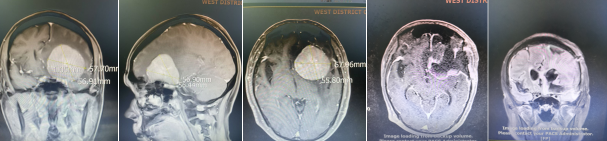

颅内肿瘤